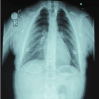

Thirteen years old female patient was referred to the periodontal clinic after her deciduous teeth were extracted to improve her oral hygiene and then to be referred to prosthetic clinic in order to construct upper and lower removable partial denture. After extra and intra oral examination; the patient had the classical signs of CCD: frontal bossing and hypertolerism with low nasal bridge (depressed nasal bridge). Attempt to place her shoulder adjacent to the midline, relatively short stature (Figure 1). Chest X-ray revealed hypoplastic clavicle with small high lying scapula (Figure 2), anterioposterior skull view showed macrcephale with widened anterior fontanel and sagital suture (Figure 3).

Figure 2. Chest X-ray for the older girl.